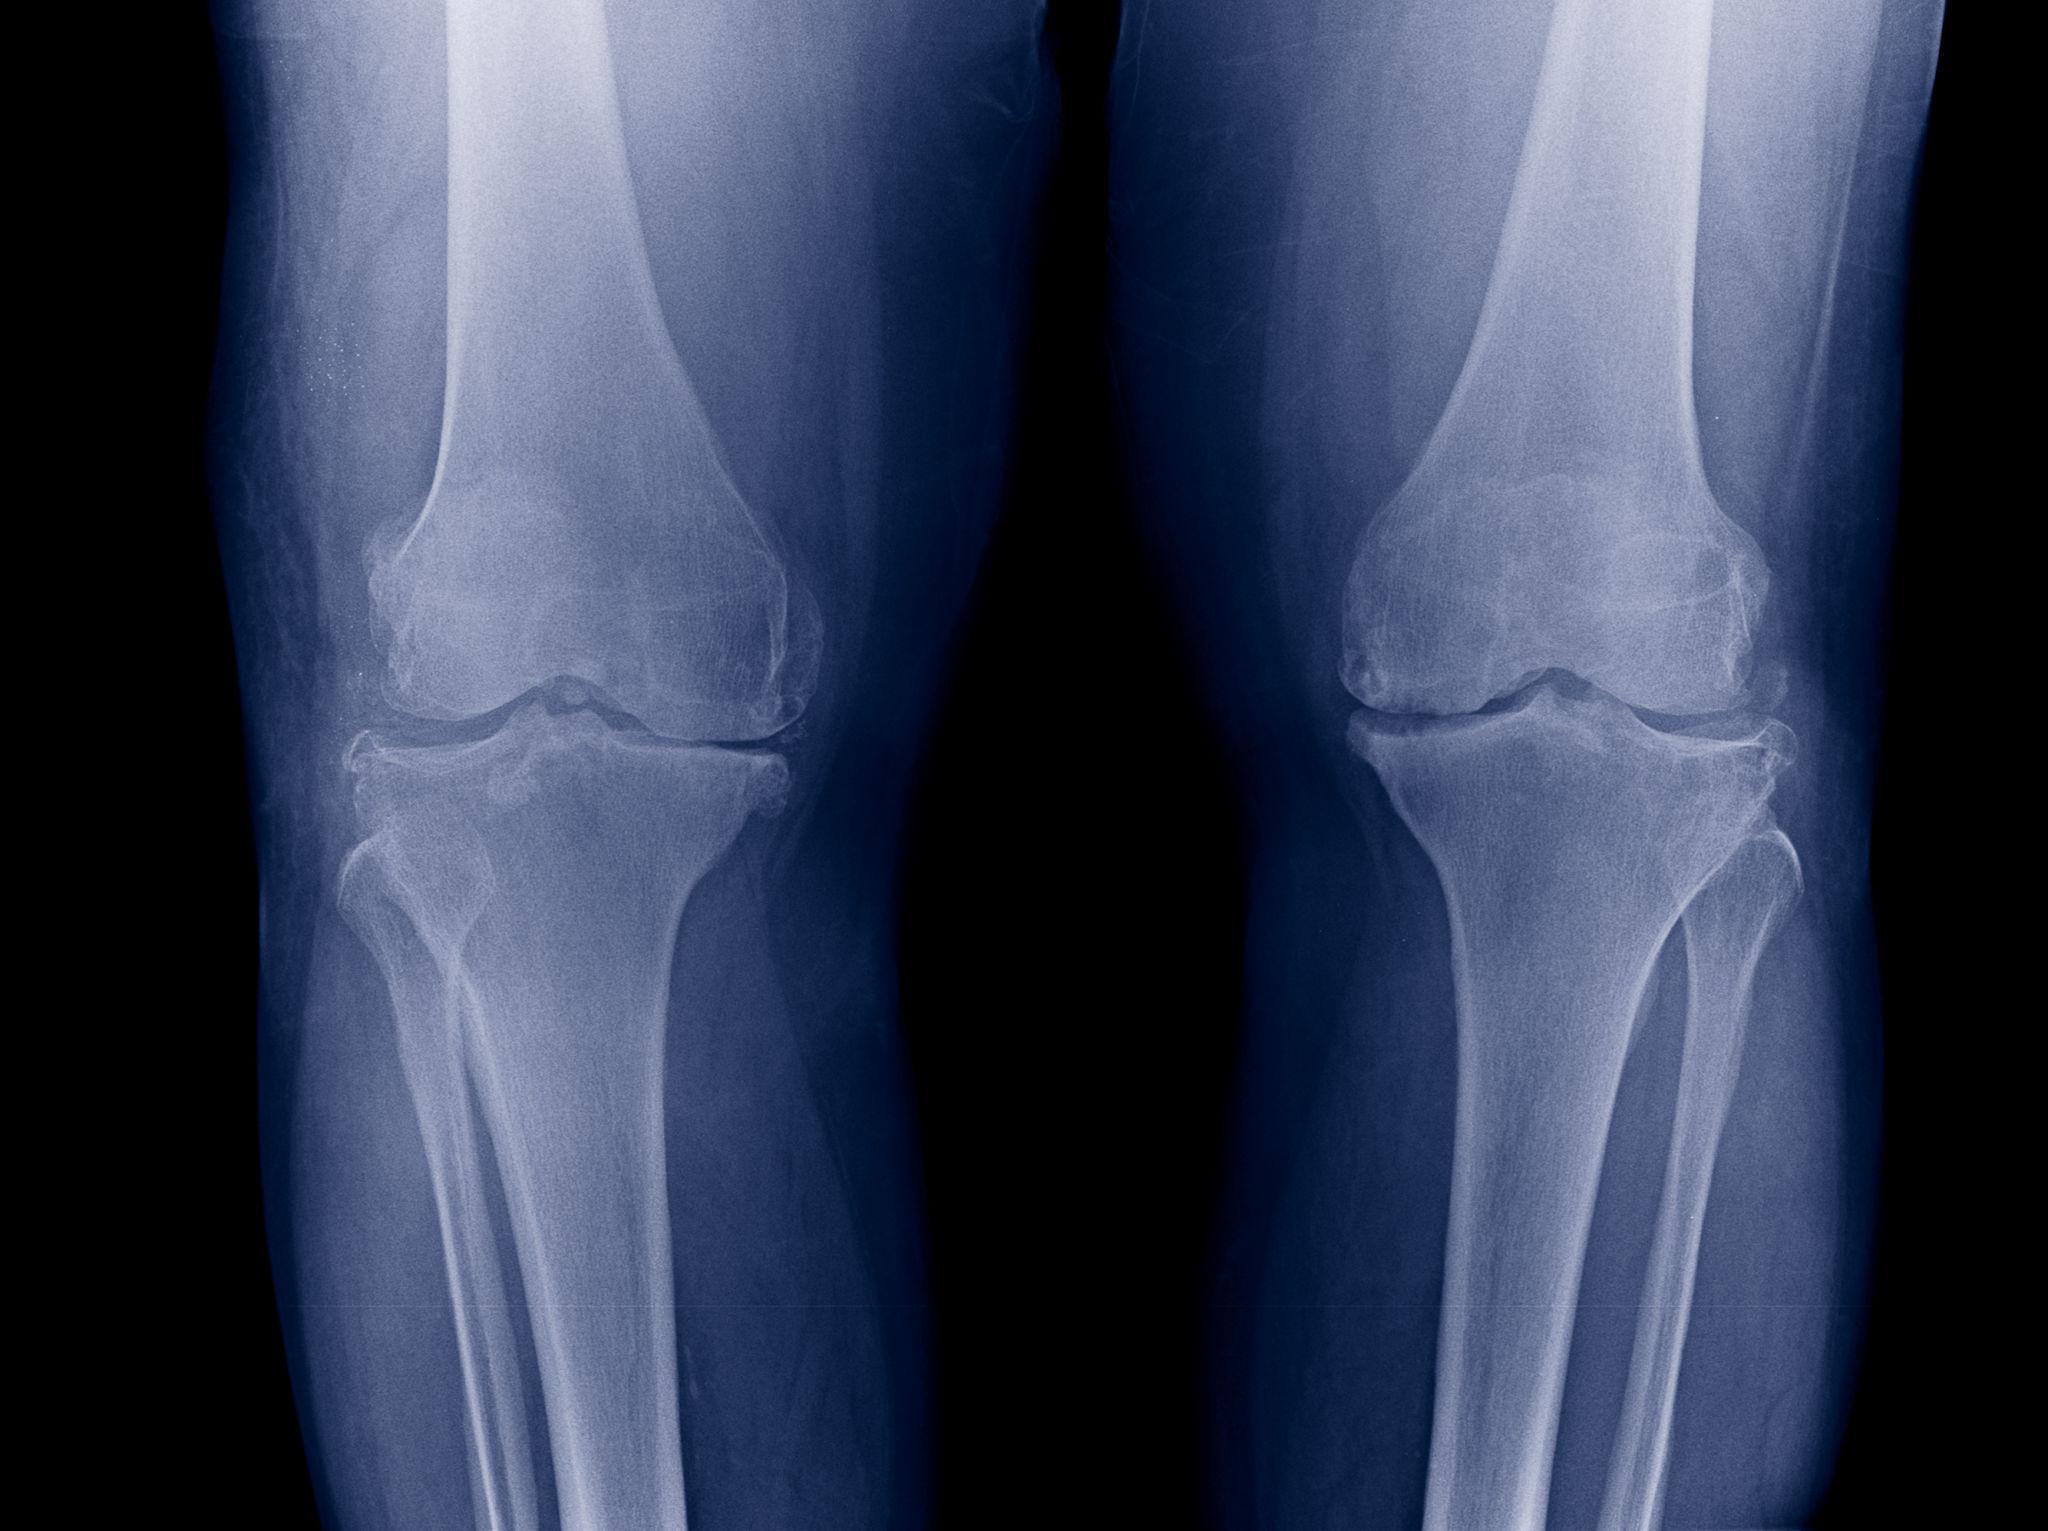

Imaging tests often confirm the severity of arthritis. If X-rays show:

Your orthopedic specialist may recommend Total Knee Replacement.